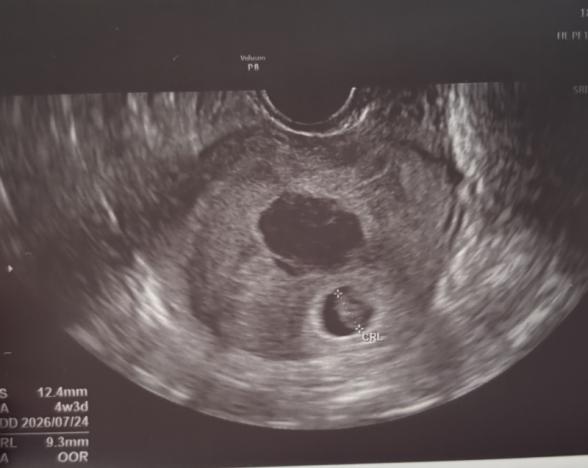

胎芽が9.4mmに対して

胎嚢が12.4mm